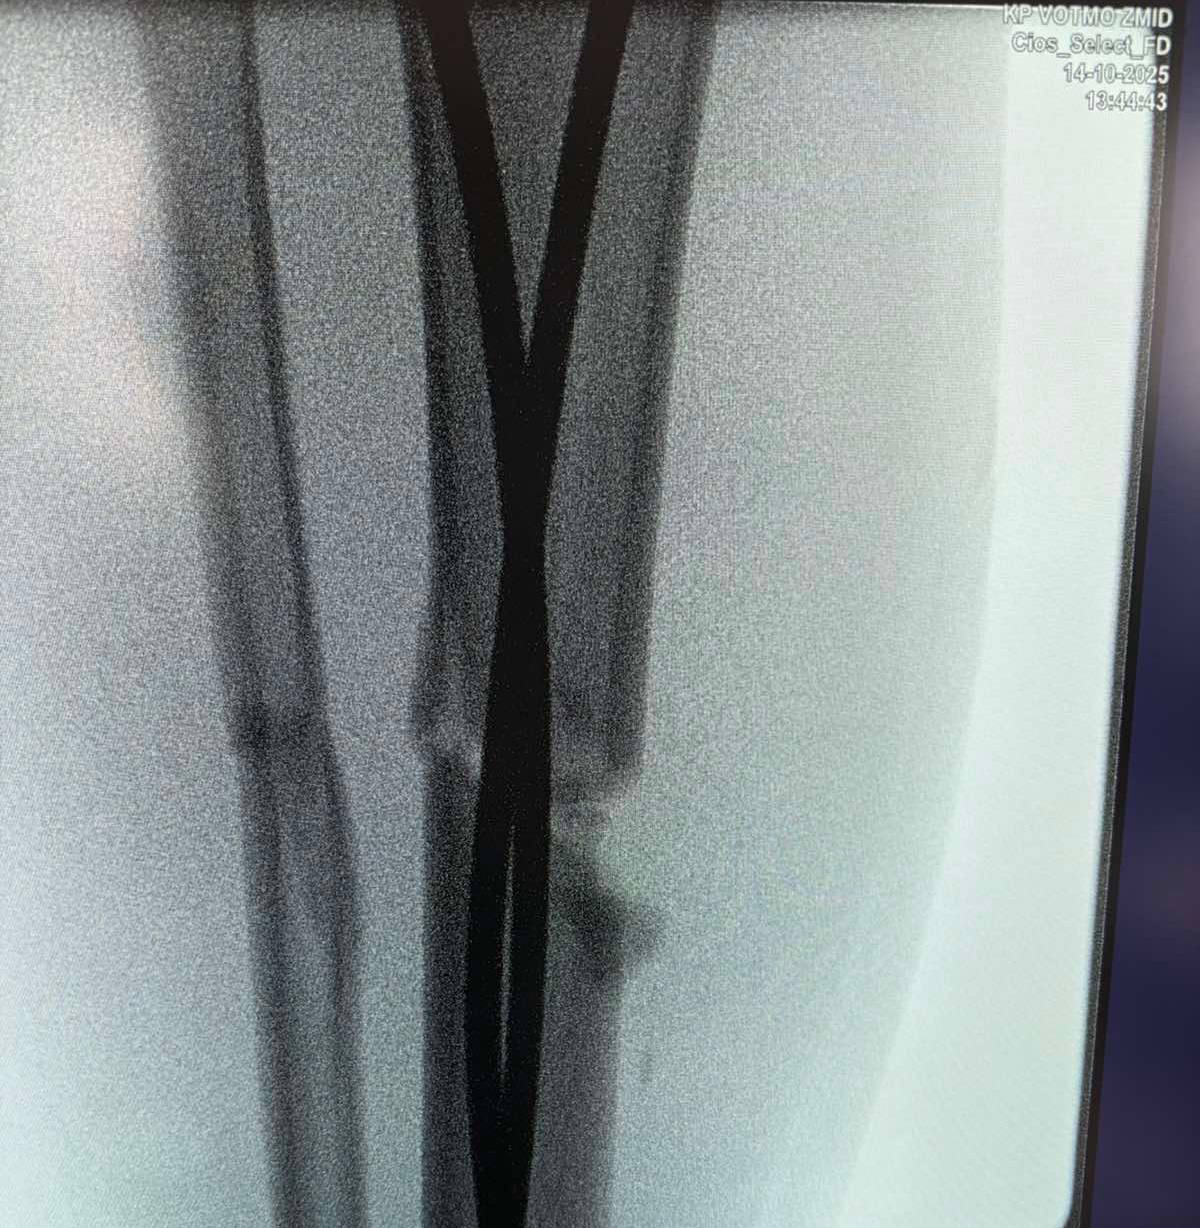

Інтрамедулярний остеосинтез – хірургічний метод лікування переломів, що дає можливість уникнути тривалого носіння гіпсових пов’язок та швидко реабілітуватися. Цей метод полягає у введенні в кістку гнучких титанових стержнів, які виконують функцію внутрішнього каркаса та фіксують кісткові відламки. Оперативне втручання проводять під рентген-контролем.

Наслідки падіння для 13-річного Максима – перелом стегнової кістки зі зміщенням і кісток гомілки.«Переломи дуже серйозні, – каже дитячий ортопед-травматолог Богдан Петерчук. – Попри це, завдяки інтрамедулярному остеосинтезу через два дні після операції Максим вже рухає ногою та швидко реабілітується. Оперативне втручання ми зробили через невеликі розрізи на стегні та гомілці».